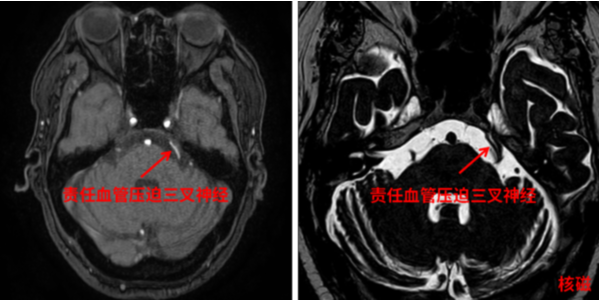

8月17日,手术如期举行,由关宇光主任担任主刀,赵萌副主任医师等为助手。术中,关宇光主任探查患者三叉神经全程,仔细寻找哪一段神经被“责任血管”压迫,见小脑上动脉压迫三叉神经根部,游离动脉,在三叉神经与“责任血管”之间垫入涤纶垫片,将神经和血管隔离开,使血管不再压迫三叉神经。整个手术耗时2小时30分。术后当天,折磨贾老伯多年的面部剧痛顽疾立即消失。